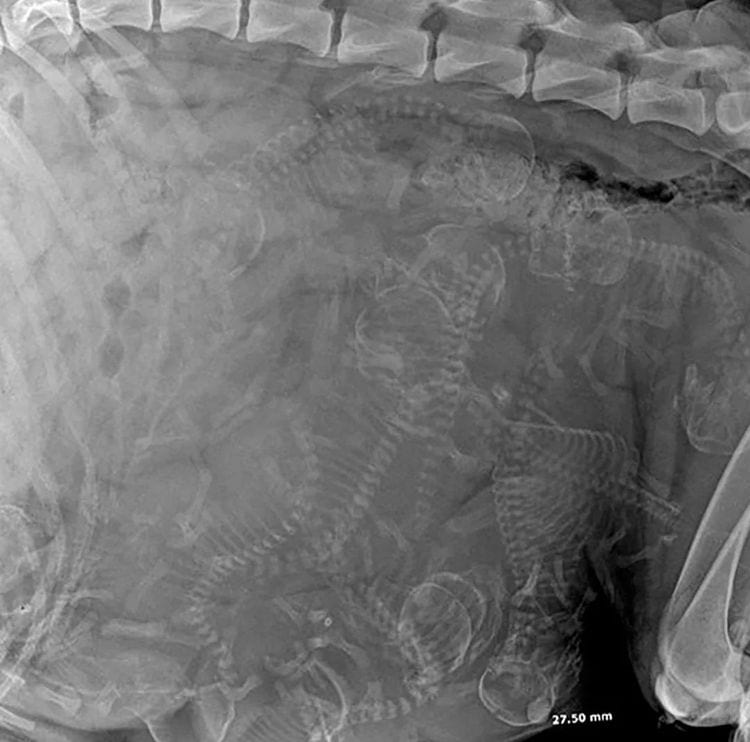

Рентгенограмма живота беременной собаки